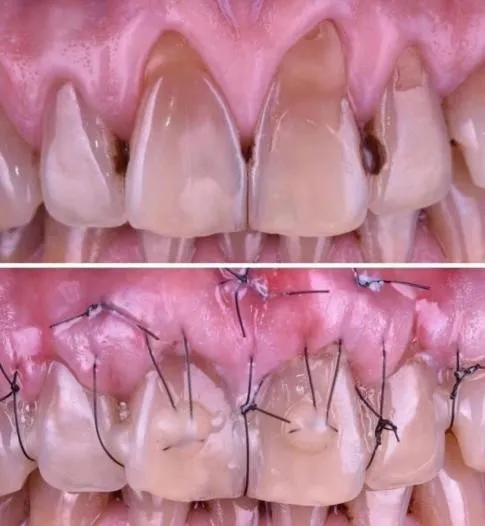

近期进行过牙科治疗:洗牙、龈下刮治、牙冠修复等,这些治疗可能会导致暂时性敏感,通常4至6周内消失;最常见的是在洗牙、刮治后,长期沉积于牙根面的牙结石被去除,牙根面暴露(如图),引发根面牙本质敏感;通常在治疗后1周内,敏感最为严重。

但此类敏感的原因在于牙结石的堆积,而非治疗本身,且1个月左右敏感症状基本消退。所以,希望大家不要因为敏感而对治疗产生抵触情绪。

⑤ 牙周手术牙龈移植:将牙龈组织重新覆盖根面,保护牙根并降低敏感性。如图: